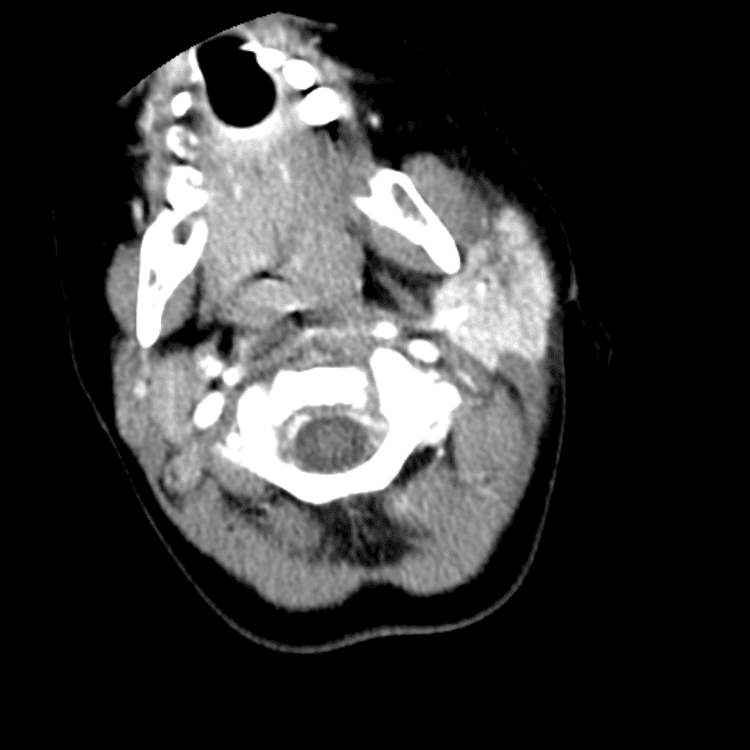

Head and Neck

Practice

Simulates call by including subtle or difficult cases and some normals.

27 cases